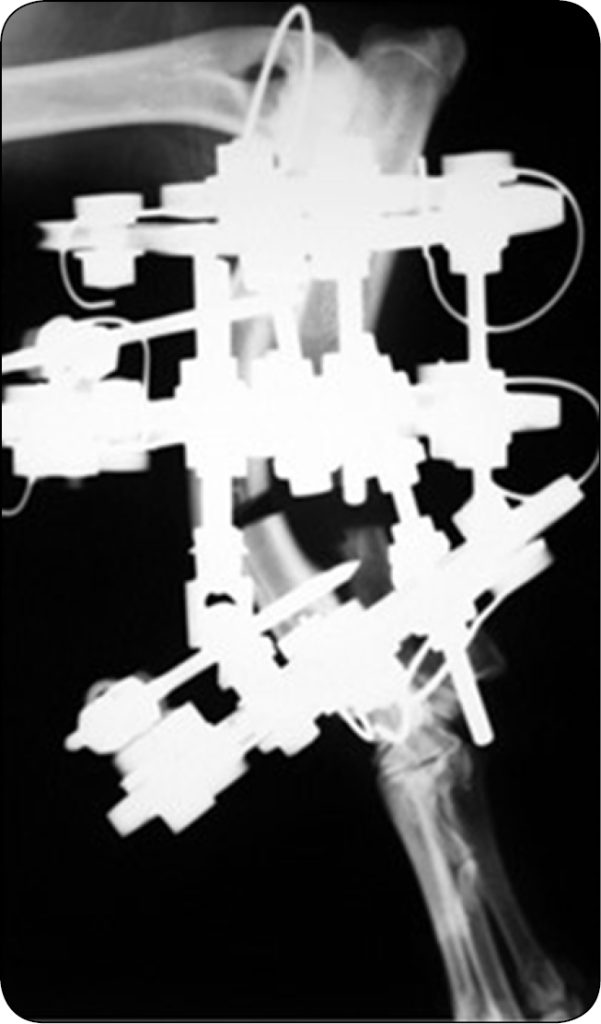

Osteotomię wykonywano piłą oscylacyjną lub osteotomem, zależnie od preferencji chirurga. Deformację skrętną korygowano bezpośrednio o wartość ustaloną podczas planowania przedoperacyjnego (ryc. 3a-b). W tym celu zawiasy odłączano od bloku dystalnego, kikut dystalny obracano o żądaną wartość, a następnie zawiasy ponownie łączono z blokiem dystalnym we wcześniej obliczonej pozycji.

Ponieważ blok dystalny został przekręcony, punkty połączeń zawiasów z blokiem dystalnym różniły się od tych przed wykonaniem obrotu (ryc. 4a-b).